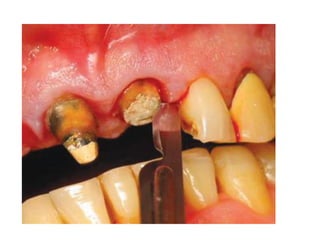

Injury to Inferior Alveolar Nerve

Cause

-Excessive extraction force in case of curved

roots

-Sectioning the tooth all the way inferiorly

Prevention

-Proper exposure & bone removal

-Controlled force

-Careful setioning, leaving a shell of the tooth

Injury to the Lingual Nerve

-Placement of the retromolar incision far

lingually

-Sectioning the tooth all the way to the lingual

cortex

-Proper incision

-Careful sectioning, leaving a shell of the tooth